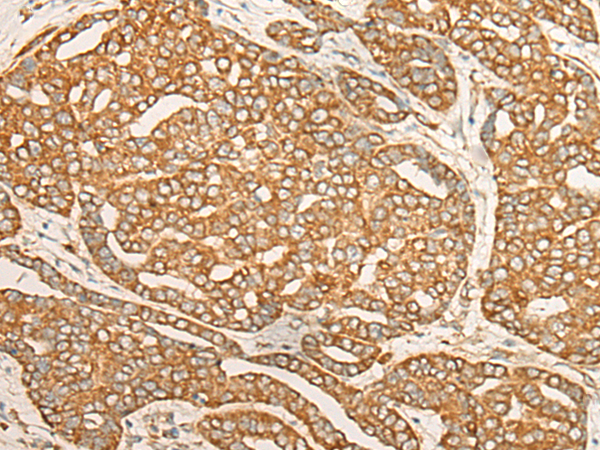

This gene encodes a member of a multienzyme complex that functions in mediating the attachment of amino acids to their cognate tRNAs. The encoded protein ligates L-aspartate to tRNA(Asp). Mutations in this gene have been found in patients showing hypomyelination with brainstem and spinal cord involvement and leg spasticity. Alternative splicing results in multiple transcript variants. [provided by RefSeq, Jun 2014] |

ELISA, IHC |

DARS1 |

aspartyl-tRNA synthetase 1 |

IHC positive control: |

Human liver cancer |

IHC Recommend dilution: |

30-150 |